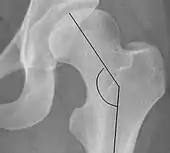

| Cervical diaphyseal angle | ![]() |

The angle formed between the femoral neck and femoral diaphysis | 120° to 140°

|